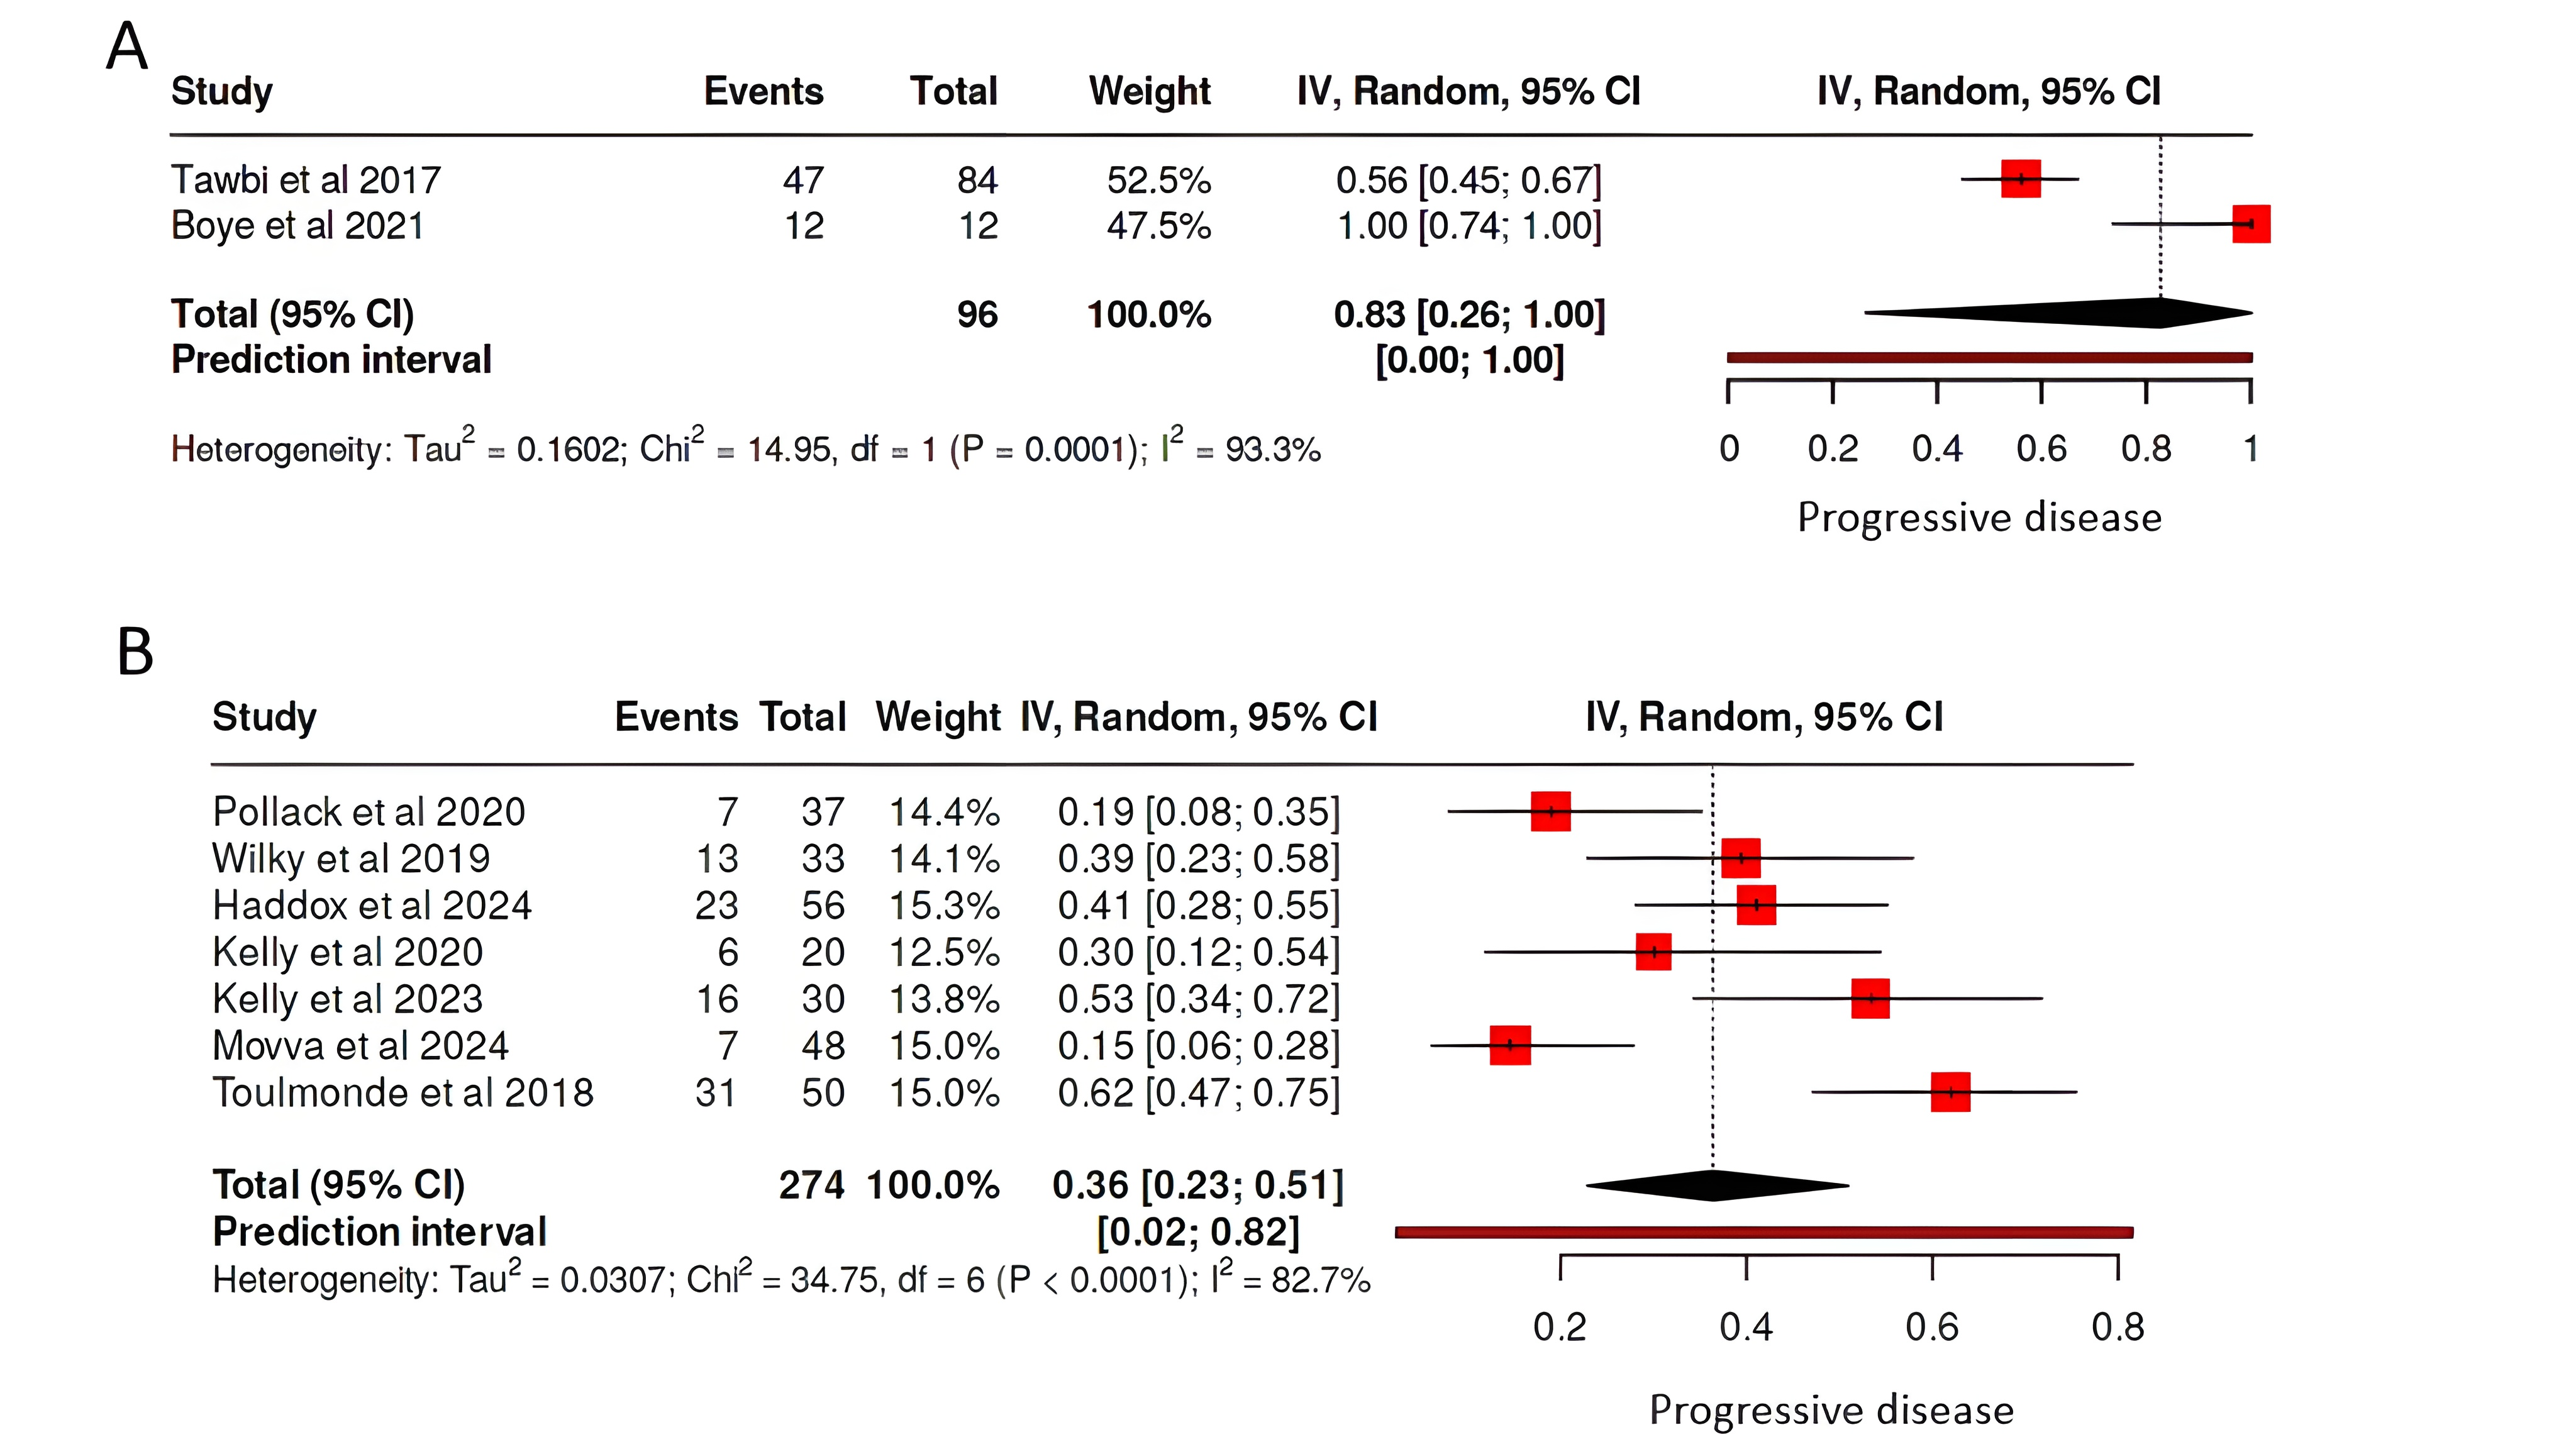

A total of 398 articles were identified through the search. After an initial review, 11 articles were excluded due to duplication and non-English language. The remaining 387 articles underwent title and abstract screening, during which 64 articles were excluded for not meeting the inclusion criteria. Consequently, 323 articles proceeded to full-text screening, and 93 were excluded due to unretrievable data, editorials, letters, or incomplete information. The remaining articles were then assessed for eligibility, resulting in 229 articles [1, 3, 4, 6-231] with 1,002 patients meeting the inclusion criteria and included in the study [Fig. 1].